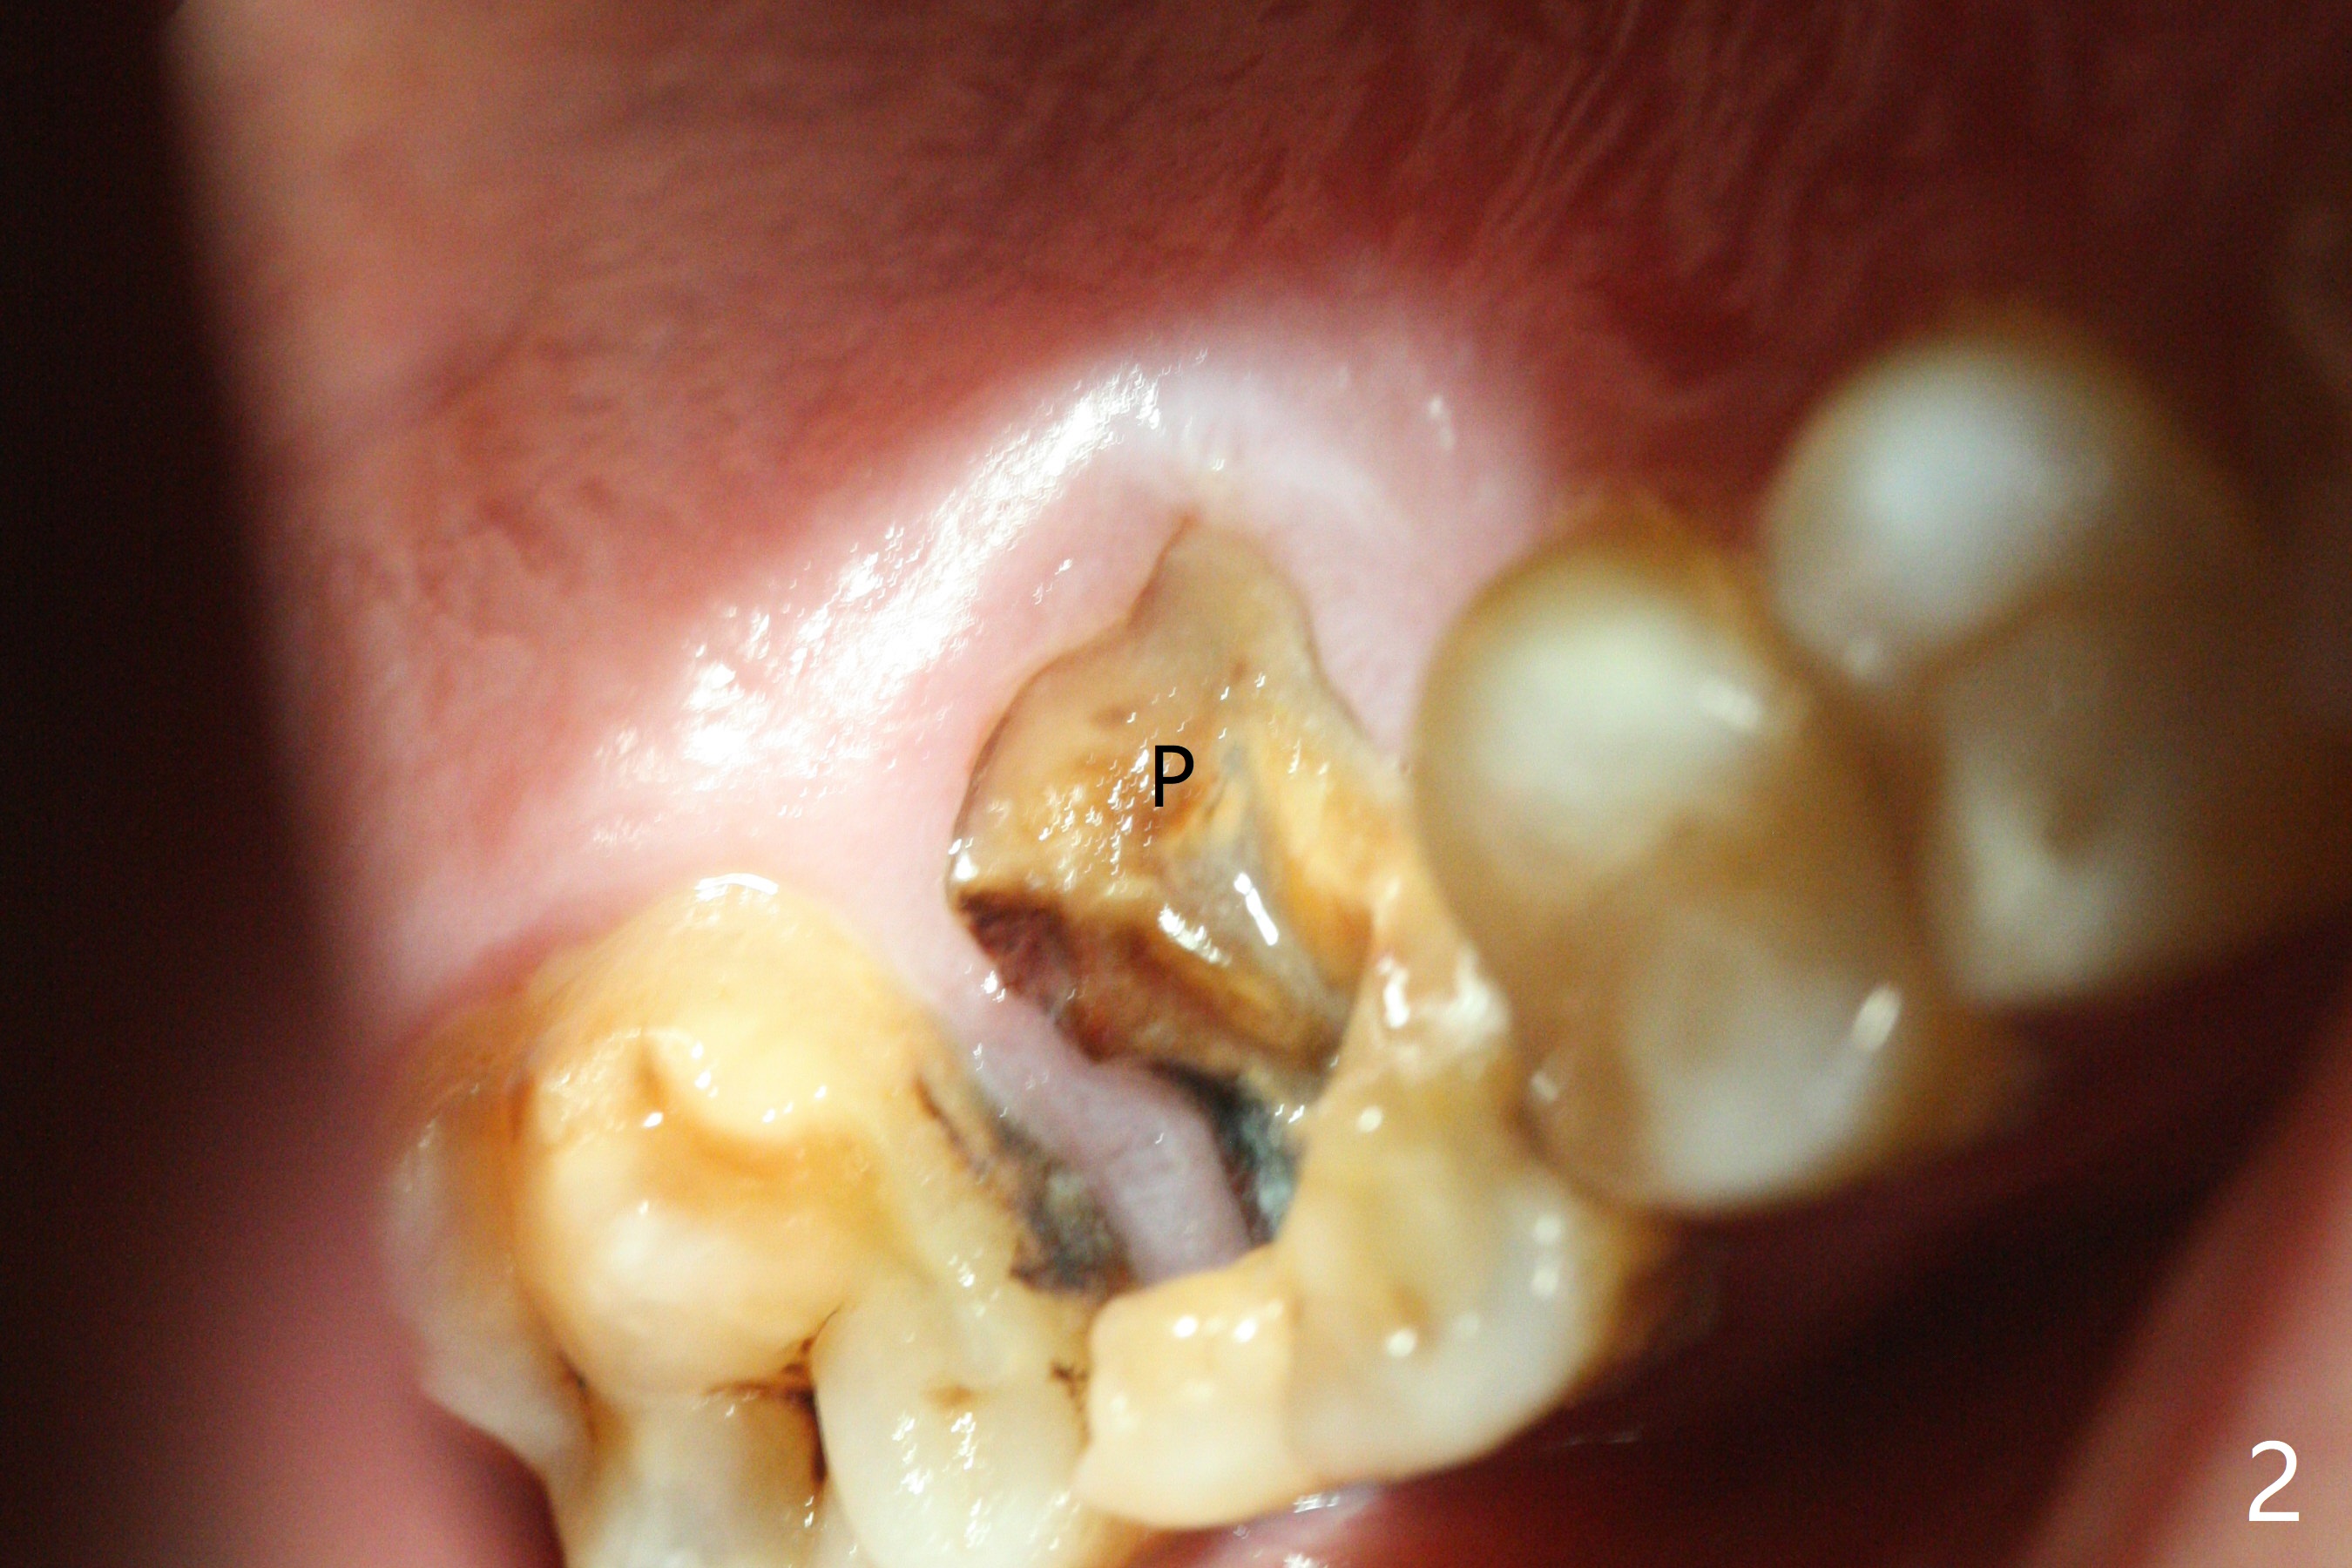

A 48-year-old man returns for implant at #14 after endo consult (Fig.1). The tooth appears to have fractured subgingival palatal (Fig.2,3 P). The furca is thin (Fig.3 *). A 5x10 mm implant will be placed slightly away palatal because of bone loss (Fig.4). Since the mesiobuccal (Fig.5 MB) and distobuccal (DB) sockets are close to the osteotomy (green), gauze with 1:50,000 Epinephrine (to reduce hemorrhage during sinus lift) will be placed away from the osteotomy (Fig.6 white area). In fact socket shield is conducted palatal.